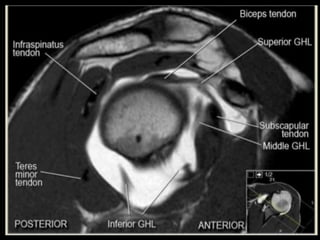

Shoulder

Joint.